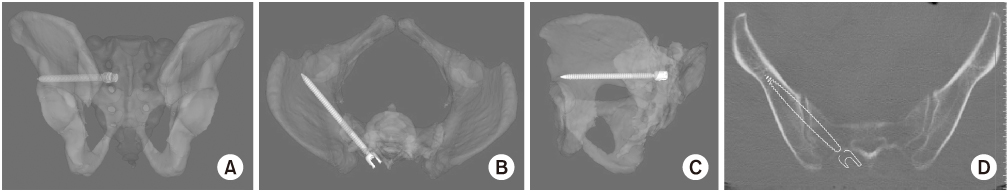

Fig. 6

(A, B) The variable of basal height could be measured using the three-dimensional biplanar image in the opposite side.

Fig. 7

(A, B) The safe zone of the 2nd sacrum can be observed easily in the lateral radiographs of pelvis and increased inversely according to the sacral dysmorphism.